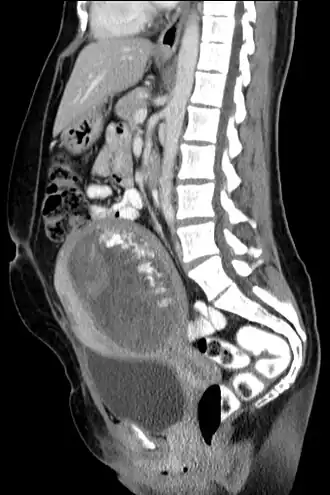

Tomografia computadorizada, vista sagital.